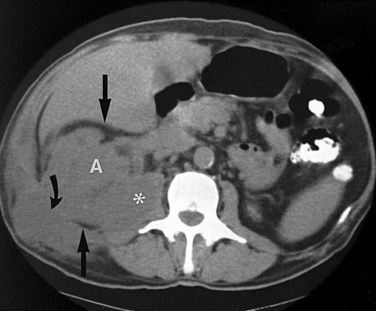

These studies are commonly used to evaluate patients initially for complicated UTIs or factors or to reevaluate patients who do not respond after 72 hours of therapy (see later). Ultrasonography (Fig. 10–19) and CT show renal enlargement, hypoechoic or attenuated parenchyma, and a compressed collecting system. They also may delineate focal bacterial nephritis and obstruction. When parenchymal destruction becomes pronounced, a more disorganized parenchyma and abscess formation associated with complicated renal and perirenal infections may be identified (Soulen et al, 1989).

Figure 10–19 Acute pyelonephritis. Ultrasound image of the right kidney demonstrates renal enlargement, hypoechoic parenchyma, and compressed central collecting complex (arrows).

(From Schaeffer AJ. Urinary tract infections. In: Gillenwater JY et al, editors. Adult and pediatric urology. Philadelphia: Lippincott William & Wilkins; 2002. p. 211–72.)

When the response to therapy is slow or the urine continues to show infection, an immediate reevaluation is mandatory. Urine and blood cultures must be repeated and appropriate alterations in antimicrobial therapy made on the basis of susceptibility testing. CT is indicated to attempt to identify unsuspected obstructive uropathy, urolithiasis, or underlying anatomic abnormalities that may have predisposed the patient to infection, prevented a rapid therapeutic response, or caused complications of the infectious process, such as renal or perinephric abscess. In patients with fever lasting longer than 72 hours, CT is most helpful for ruling out obstruction and identifying renal and perirenal infections (Soulen et al, 1989). Radionuclide imaging may be useful to demonstrate functional changes associated with acute pyelonephritis (decrease in renal blood flow, delay in peak function, and delay in excretion of the radionuclide) (Fischman and Roberts, 1982) and cortical defects associated with vesicoureteral reflux.